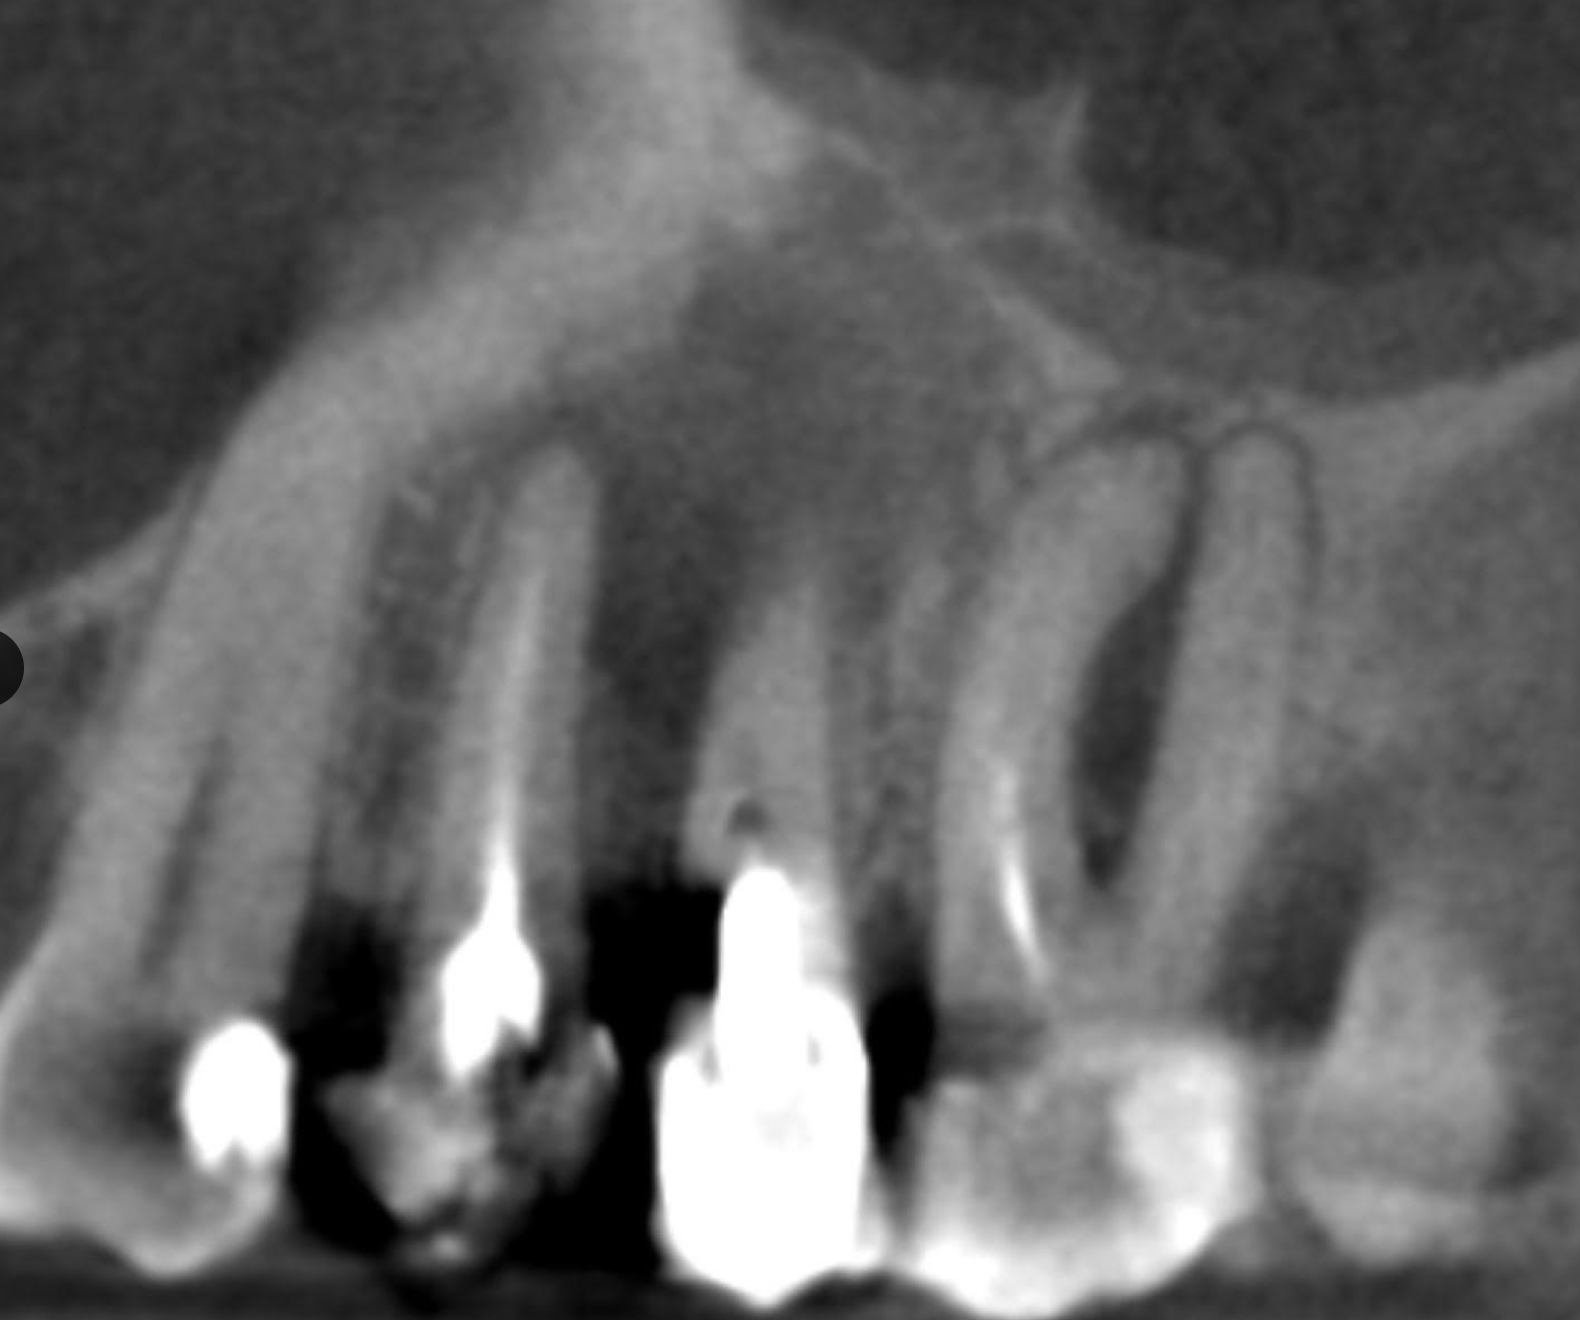

This webinar aims to offer practical and clear guidance on evaluating the best treatment options for these cases. Key factors such as the presence of broken instruments, the type of post use, restorative considerations and anatomical variations will be thoroughly discussed to aid in making informed clinical decisions.